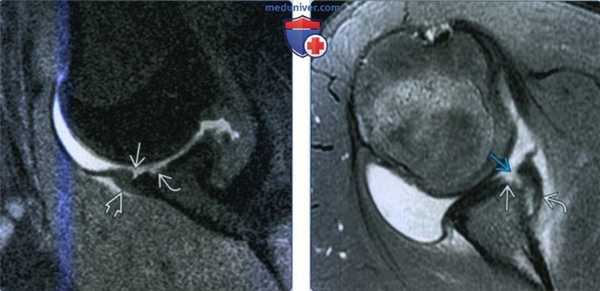

(Слева) На сагиттальном рисунке показан расширенный разрыв губы с отделенными передними и задними участками. У большинства пациентов с таким 180° разрывом наблюдается передняя нестабильность и появляется боль после переднего вывиха или подвывиха.

(Справа) На осевой МР-артрограмме PDBИ FS у футболиста после самостоятельного вправления переднего вывиха определяется разрыв с захватом передней и задней губы. Разрывы задней губы обусловлены тракцией задней капсулы и связок.

(Слева) На фронтальной косой МР-артрограмме Т2ВИ FS у этого же пациента определяется разрыв, переходящий через нижнюю губу, следовательно, захватывающий каудальные 180° губы.

(Справа) На фронтальной (слева) и осевой (справа) МР-артрограммах Т2ВИ F5 у футболиста 18 лет с болью и передней нестабильностью после эпизода подвывиха определяется 360° разрыв губы. Разрыв захватывает верхнюю, нижнюю, переднюю и заднюю губу. Такие повреждения называются также передними и задними разрывами верхней губы IX типа.